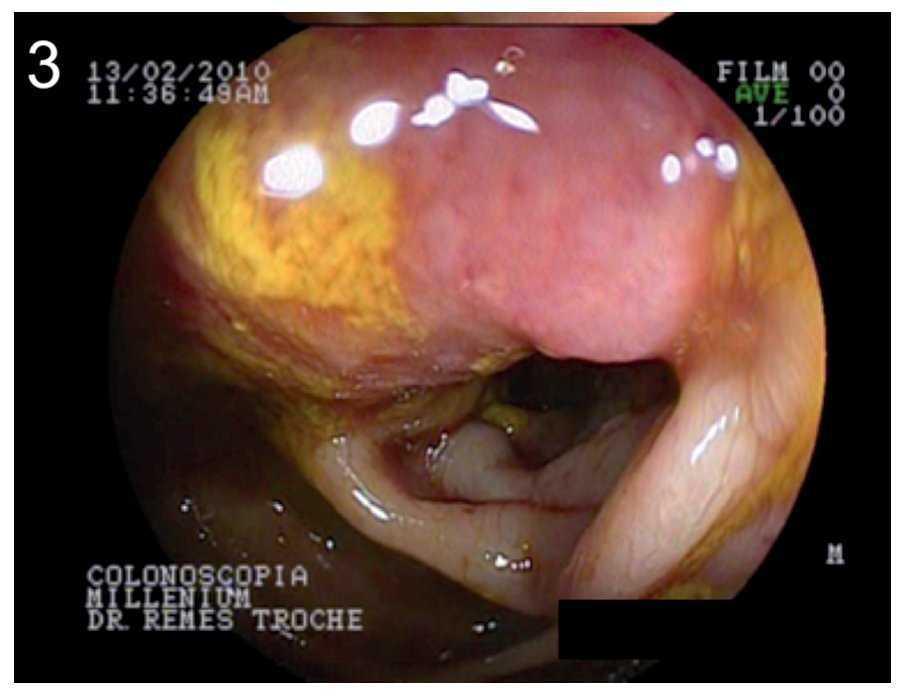

Se realizó manometría esofágica con catéter de estado sólido que demostró la presencia de esfínter esofágico superior hipotenso (presión basal promedio de 23 mmHg), relajación incompleta del esfínter (porcentaje de relajación del 58%) e incoordinación faringo-esofágica (Figura 2). Con dichos hallazgos se diagnosticó una miopatía inflamatoria clasificada como dermatopolimiositis. Se inició tratamiento con bolos de metilprednisolona, antibióticos profilácticos (cefuroxima) y soporte nutricio enteral. Ante la sospecha clínica de que la dermatopolimiositis fuera un sindrome paraneoplásico, se midieron marcadores tumorales: alfafetoproteína (AFP) de 3.5 ng/mL (normal < 10 ng/mL), CA 19-9 de 5.7 ng/mL (normal < 35 ng/mL) y antigeno carcinoembrionario (ACE) de 15.3 ng/mL (normal no fumador < 5 ng/mL). Debido a la elevación del ACE se realizó endoscopía del tracto digestivo superior encontrando sólo la presencia de candidiasis esofágica grado I de la clasificación de Kodsi; sin embargo, la colonoscopia demostró la presencia de una lesión de aspecto infiltrante, a 15 o 20 cm de la margen anal, exofítica, friable que ocluía aproximadamente 60% de la luz del sigmoides (Figura 3). Se tomaron biopsias que demostraron la presencia de un adenocarcinoma moderadamente diferenciado. Diez días despúes de su internamiento y con mejoría de su estado nutricio (albúmina 3.4 g/dL), se realizó laparotomía exploradora en la que se detectó la lesión neoplásica en sigmoides. Se realizó colectomía subtotal con colostomía en asa y linfadenectomia locoregional sin complicaciones en el postoperatorio. Macroscópicamente se observo una neoplasia infiltrante hacia la serosa (Figura 4A y B) y los hallazgos histopatológicos corroboraron el adenocarcinoma moderadamente diferenciado de tipo intestinal (Figura 4C). Se encontraron cinco de cinco ganglios positivos.

¿ Figura 3. Lesión infiltrante, exofítica y friable, que ocluye 60% de la luz del sigmoides a una distancia de entre 15 cm a 20 cm de la margen anal, compatible con adenocarcinoma moderamente diferenciado de colon.